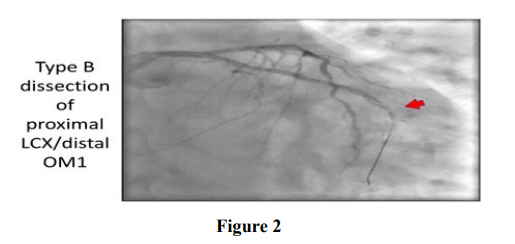

Among the 806 patients that underwent percutaneous coronary intervention during 3 years (2014-2017) period at Cath-Lab of Cardiology Department of Dow University of Health Sciences Karachi, 28 (3.4%) patients had extensive dissection (defined as a dissection extending beyond the limits of the dilated angioplasty balloon) in the coronary artery, Dissection type was found A in 12 (42.8%) cases, B in 20 (71.4%), C in 5 (17.5%), D in 2 (7.1%), E in 1 (3.5%), and F in 0 (0.0%) Table1.

Dissection occurred in 6 patients with balloon angioplasty and in 22 patients during procedure of angioplasty with stenting. Overall, final dissections occurred with increased frequency, as expected in longer and more complex lesions, 10 (35.7%) patients with left anterior descending artery, in 6 (21.4%) patients with side branch- es of the LCX. In 12 (42.8%) patients with RCA complicated by propagating dissection compared to other coronary arteries.